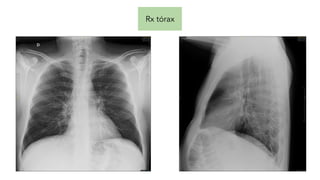

Analítica Rx tórax

Rx tórax

Pruebas complementarias Analítica Rxtórax Rx cadera derecha TC Craneal Hemocultivos Urocultivo